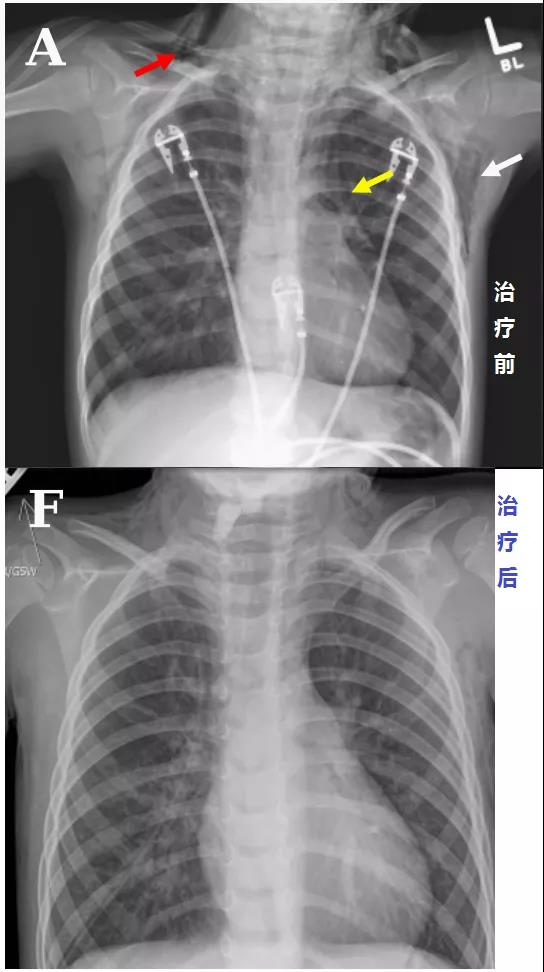

頭顱、胸部CT提示廣泛皮下氣腫、縱隔氣腫、心包積氣、甚至眼眶周圍都積氣,眼球突出!頸部無感染征象,腸管無破裂征象,看來氣體還是來自肺部。但是,肺部無感染、無肺大泡、無劇烈咳嗽,只有間質性肺氣腫。縱隔氣腫、皮下氣腫的治療,核心是根除病因,切開引流效果不像氣胸那么理想,而且縱隔切開引流還存在手術風險。找不到病因,如何是好?考慮患者是過敏體質,有皮疹,繼續(xù)呼吸機輔助呼吸,先治療過敏,肌肉注射腎上腺素、靜脈注射類固醇激素和抗組胺藥、吸入支氣管擴張劑等。經上述治療,臨床表現(xiàn)和影像學方面都有迅速的改善。隨后拔出氣管導管,口服類固醇激素出院,門診隨訪。

皮下氣腫、縱隔氣腫突然莫名其妙的就消失了!呼吸機治療可是會加重縱隔氣腫啊!這個皮下氣腫、縱隔氣腫,真的是來去一陣風啊,堪稱神出鬼沒!過敏反應一般表現(xiàn)為皮疹、皮膚瘙癢,嚴重的表現(xiàn)為休克,甚至引起喉頭水腫、氣管和支氣管痙攣及肺水腫導致呼吸困難,其他表現(xiàn)有昏迷、剝脫性皮炎型藥疹等多器官損害。沒聽說過敏反應還會導致廣泛皮下氣腫、縱隔氣腫、心包積氣,甚至眼眶周圍都積氣,眼球突出啊!過敏反應可引起急性支氣管痙攣,進而氣道壓力升高,導致肺泡破裂,空氣進入組織間隙,并沿肺間質內血管鞘進入縱隔,導致縱隔氣腫,只形成間質性肺氣腫,并不會導致我們平時所見的氣胸。這個病例提供了一個罕見的藥物過敏反應方面的臨床表現(xiàn),對于存在這種特異質的兒童來說,如果不早發(fā)現(xiàn)、早治療,隨時可能致命。另外,大家有沒有發(fā)現(xiàn),患者因咽炎口服阿莫西林,才吃了1次,后來過敏,咽炎沒繼續(xù)治療,也好了!在患者的咽炎治療過程中,阿莫西林除了引起危及生命的過敏反應,并未扮演其他有任何價值的角色!Jacob A. Kaslow, MD,Elizabeth J. Snyder, MD,Brian C, et al. Massive Facial, Neck, and Chest Air Leaks Following Amoxicillin-Related Anaphylaxis in a Young Child. AJRCCM Articles in Press. Published on 10-January-2020 as 10.1164/rccm.201908-1596IM.